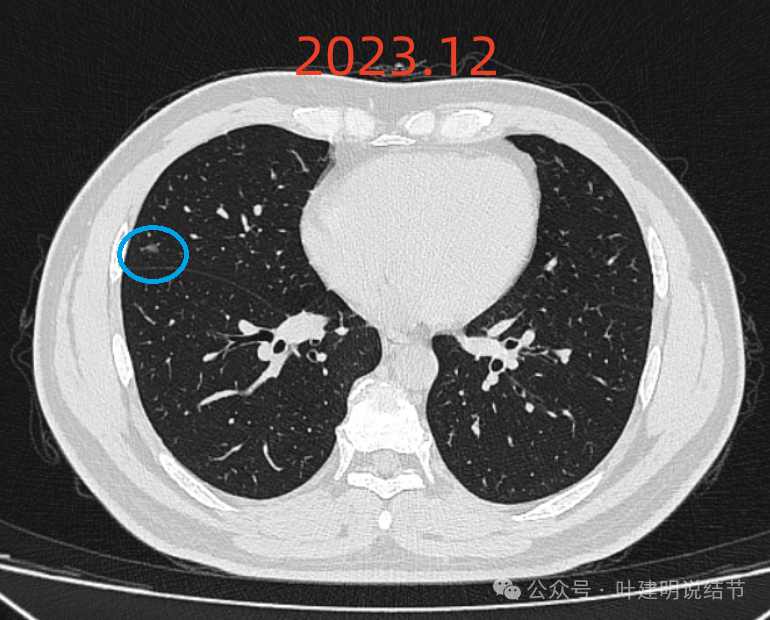

右中叶病灶仍大小相仿,边缘较平,膨胀性不明显,整体类三角形。

右中叶病灶也与2022年5月比并无进展,而且小而稳定,也没有实性成分。